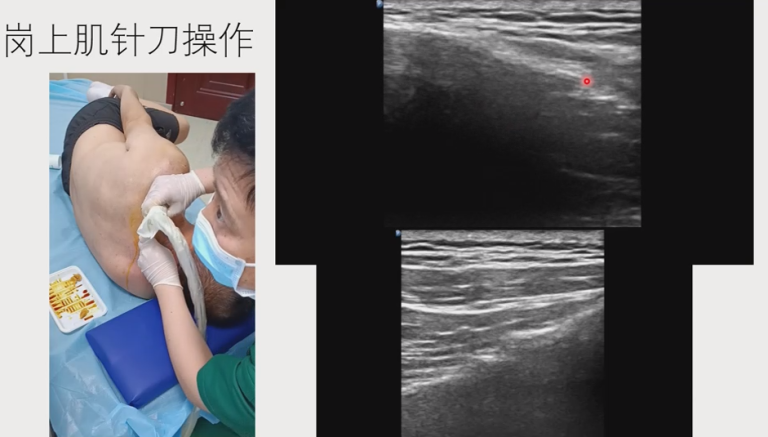

肩袖损伤,尤其是冈上肌肌腱的磨